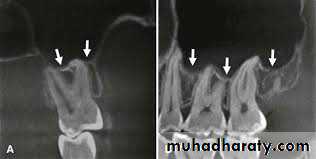

7. Displacement of the tooth into the maxillary sinus

Causesclose approximation of the teeth to the maxillary sinus.

the antral cavities may be large and may dip in between the apices of the posterior teeth or around edentulous area of isolated tooth.

With advancing age the degree of pneumatisation of the maxillary sinus increases and the antral walls become very thin. The roots of the posterior teeth are covered only by thin bone which fracture easily and result in the disappearance of the root tip during its removal.

the shape of the tooth (like the popping of an orange seed) once the extraction forceps are applied.

Prevention

Proper radiographs should be taken before the extraction to assess the proximity of the root tip to the sinus.

Support the jaw and the alveolus adequately before extraction